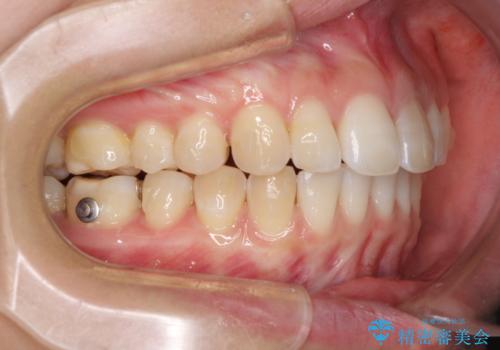

- 変色した前歯と突出した口元を気にして来院された患者様です。

口元の突出感はインビザラインにより歯列を整え、その後に、前歯をオーダーメイドタイプのオールセラミッククラウンにて補綴治療することとしました。

長時間のマウスピース装着と、患者様自身でのゴムかけに協力いただき、口元の突出感をしっかりと改善することができました。

前歯のオールセラミッククラウンもまるで本物の歯のように仕上がり、患者様には大変満足していただきました。